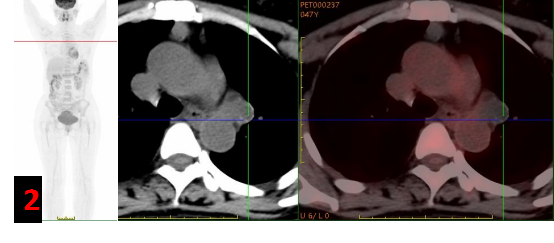

PET/CT?

主動脈弓左旁不規(guī)則混雜密度腫塊影,邊緣見斑點狀/環(huán)形鈣化灶,FDG代謝不高(SUVmax約0.3-1),考慮良性病變(圖2)。

PET/CT能夠從代謝的角度提供更有價值的診斷信息,支氣管源性囊腫往往呈低代謝或代謝缺損表現;同時PET/CT是全身檢查,對于臨床高度懷疑惡性腫瘤的患者能夠提供更全面的信息,提高診斷準確度。

本例患者由于增強CT表現不典型,臨床為排除惡性腫瘤轉移選擇PET/CT進一步明確診斷。PET/CT展示病灶無代謝,給出了良性病變的定性診斷,最終得到病理證實。